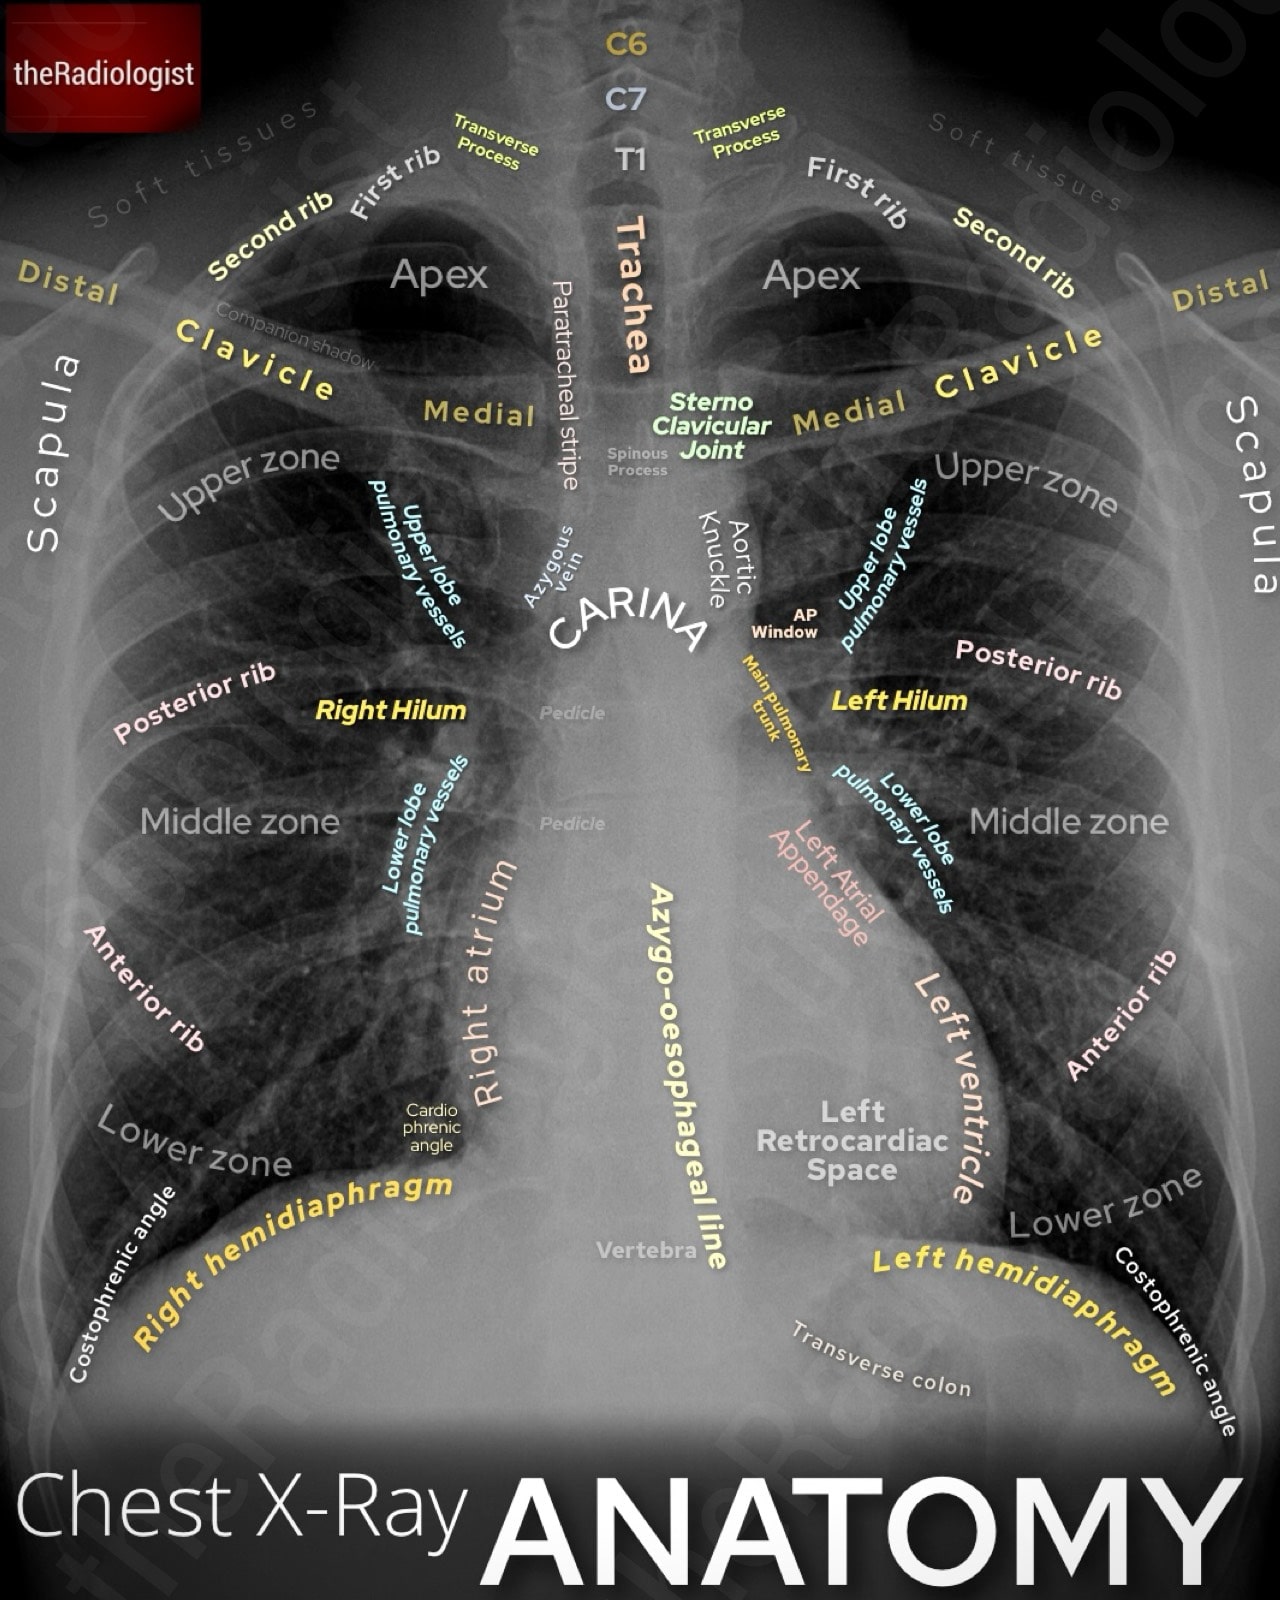

Before you jump into assessing your film, take a look at this annotated view of a PA (posterior-anterior) chest X-Ray looking at some of the basic anatomy.

Annotated view of a PA adult chest X-Ray